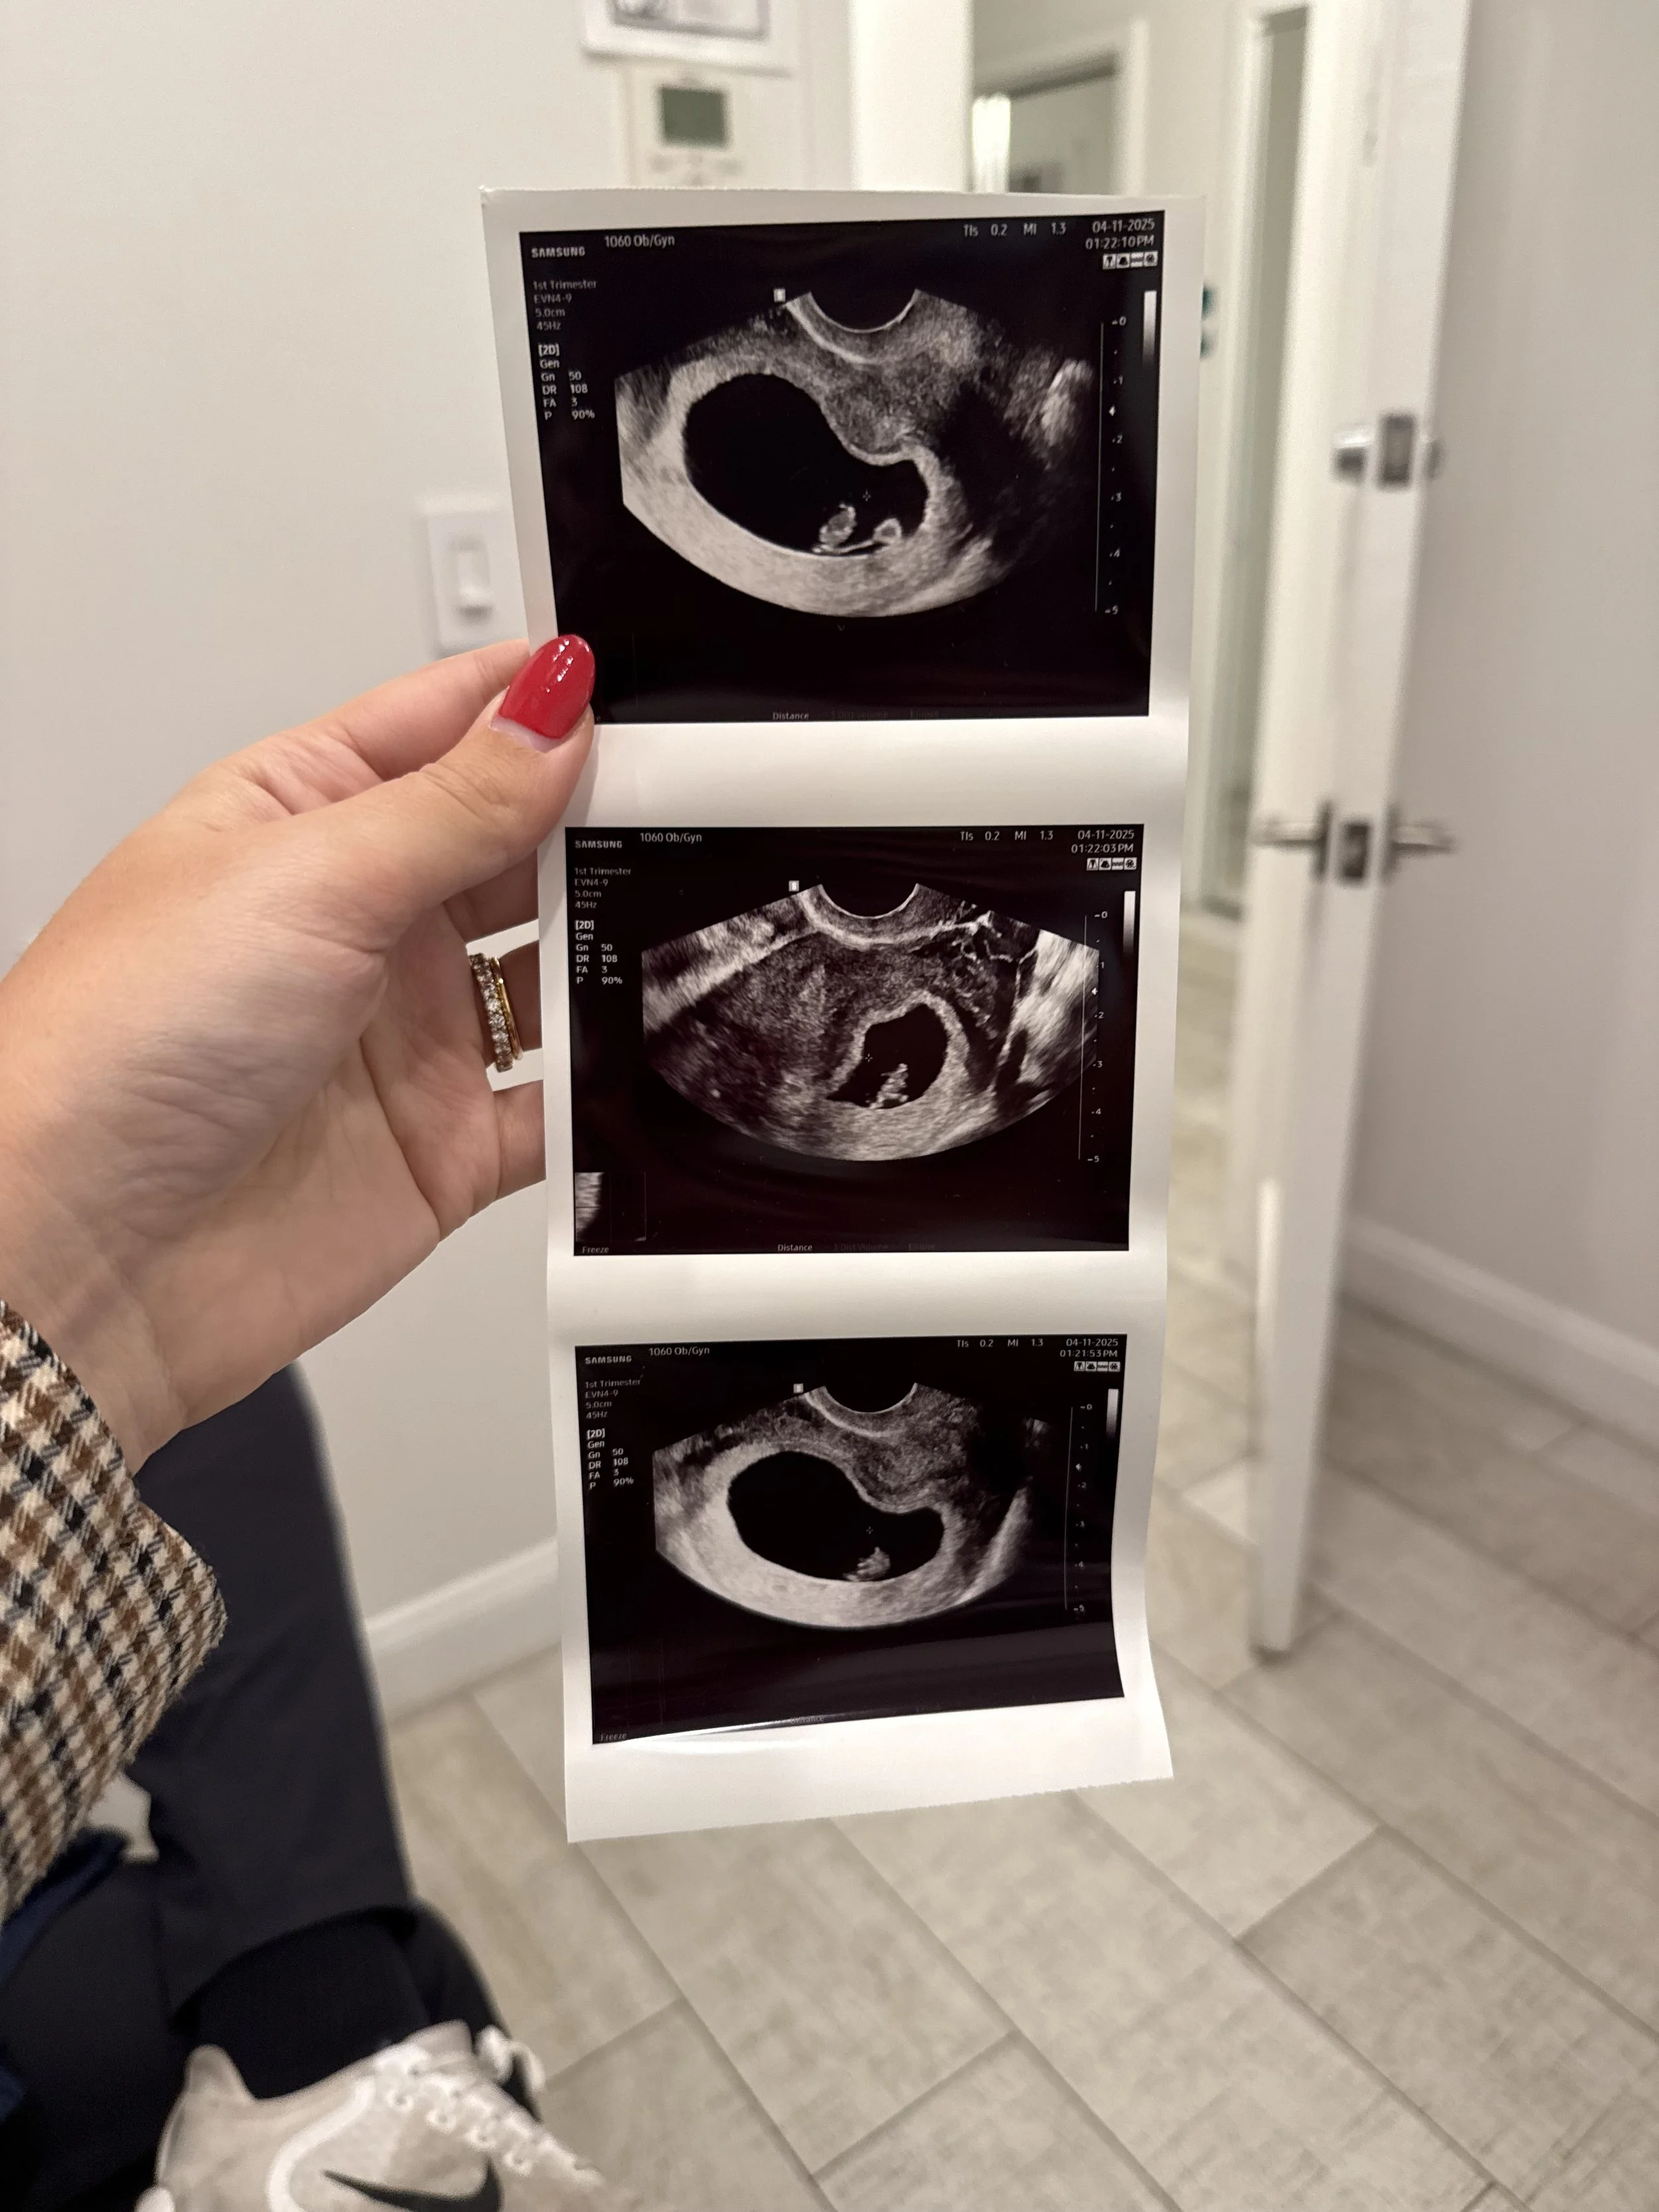

I started seeing Doctors at a new practice my best friend was going to. I was excited to have a fresh start with better care this time around. But the first 6 week scan wasn’t ideal. The Doctor saw the gestational sac and yolk sac, but no baby. My hormone levels were off due to pregnancy induced hypothyroidism, an underactive thyroid, which would require a daily medication that had to be taken in the morning on an empty stomach. I was prescribed progesterone suppositories based on my miscarriage history. I could barely concentrate at work with the feelings of anxiety. A few days later I returned to do another blood test, and they confirmed my HCG levels were doubling daily as expected… a very good sign.

I leaned on my meditation and breathing techniques between the next scan and continued to fight for this baby in the ways I knew how. Part of that was telling my family and friends early to get the support I needed. It also made this child real.. made me once again acknowledge the experience of motherhood, no matter how long or short it would be for. While the second experience sharing the news was not as surprising or special as the first time, and even with tempered expectations, the joy our loved ones had for us was so real, nonetheless.

At our 8 week appointment I returned for another ultrasound, this time to hear the baby’s heartbeat. It was a critical moment. The Doctor didn’t waste time, knowing I was anxious as I was gripping Ryan’s hand. Moments later we heard our baby’s heartbeat for the first time. It was the most beautiful sound in the world. Strong and fast, and powering this little tiny life. The baby was starting to take shape.

Time between scans still built anxiety for me, but the closer I got to the 2nd trimester, the less anxious I felt. With so many wonderful things happening in our lives at once, the weeks seemed to fly by, and suddenly I was at my 12 week scan at our hospital.

It was starting to feel real!

We found out shortly after that we are having a baby girl! Everything clicked for me the second I knew who she was, and now it’s like we’ve always known each other.  We had waited enough. Along with our families, we were ready to celebrate her life.